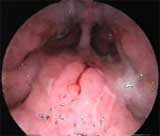

Аденоидные вегетации I степени, без признаков воспаления (риноскопия — эндоскоп 0°).

Обострение хронического аденоидита (эпифарингоскопия — эндоскоп 70°).